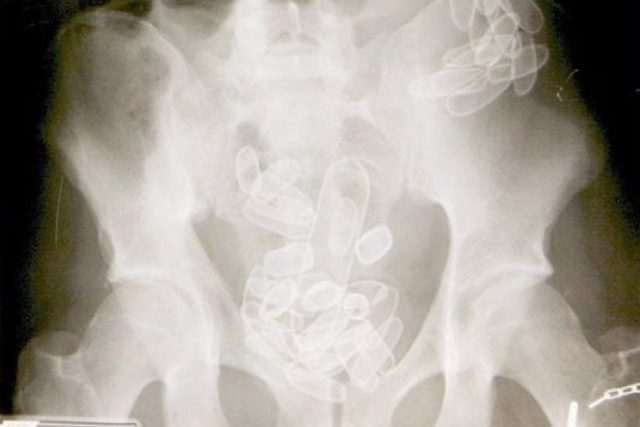

Auf Röntgenbild ersichtliche verschluckte Fingerlinge (Symbolbild) (Bild: sda)